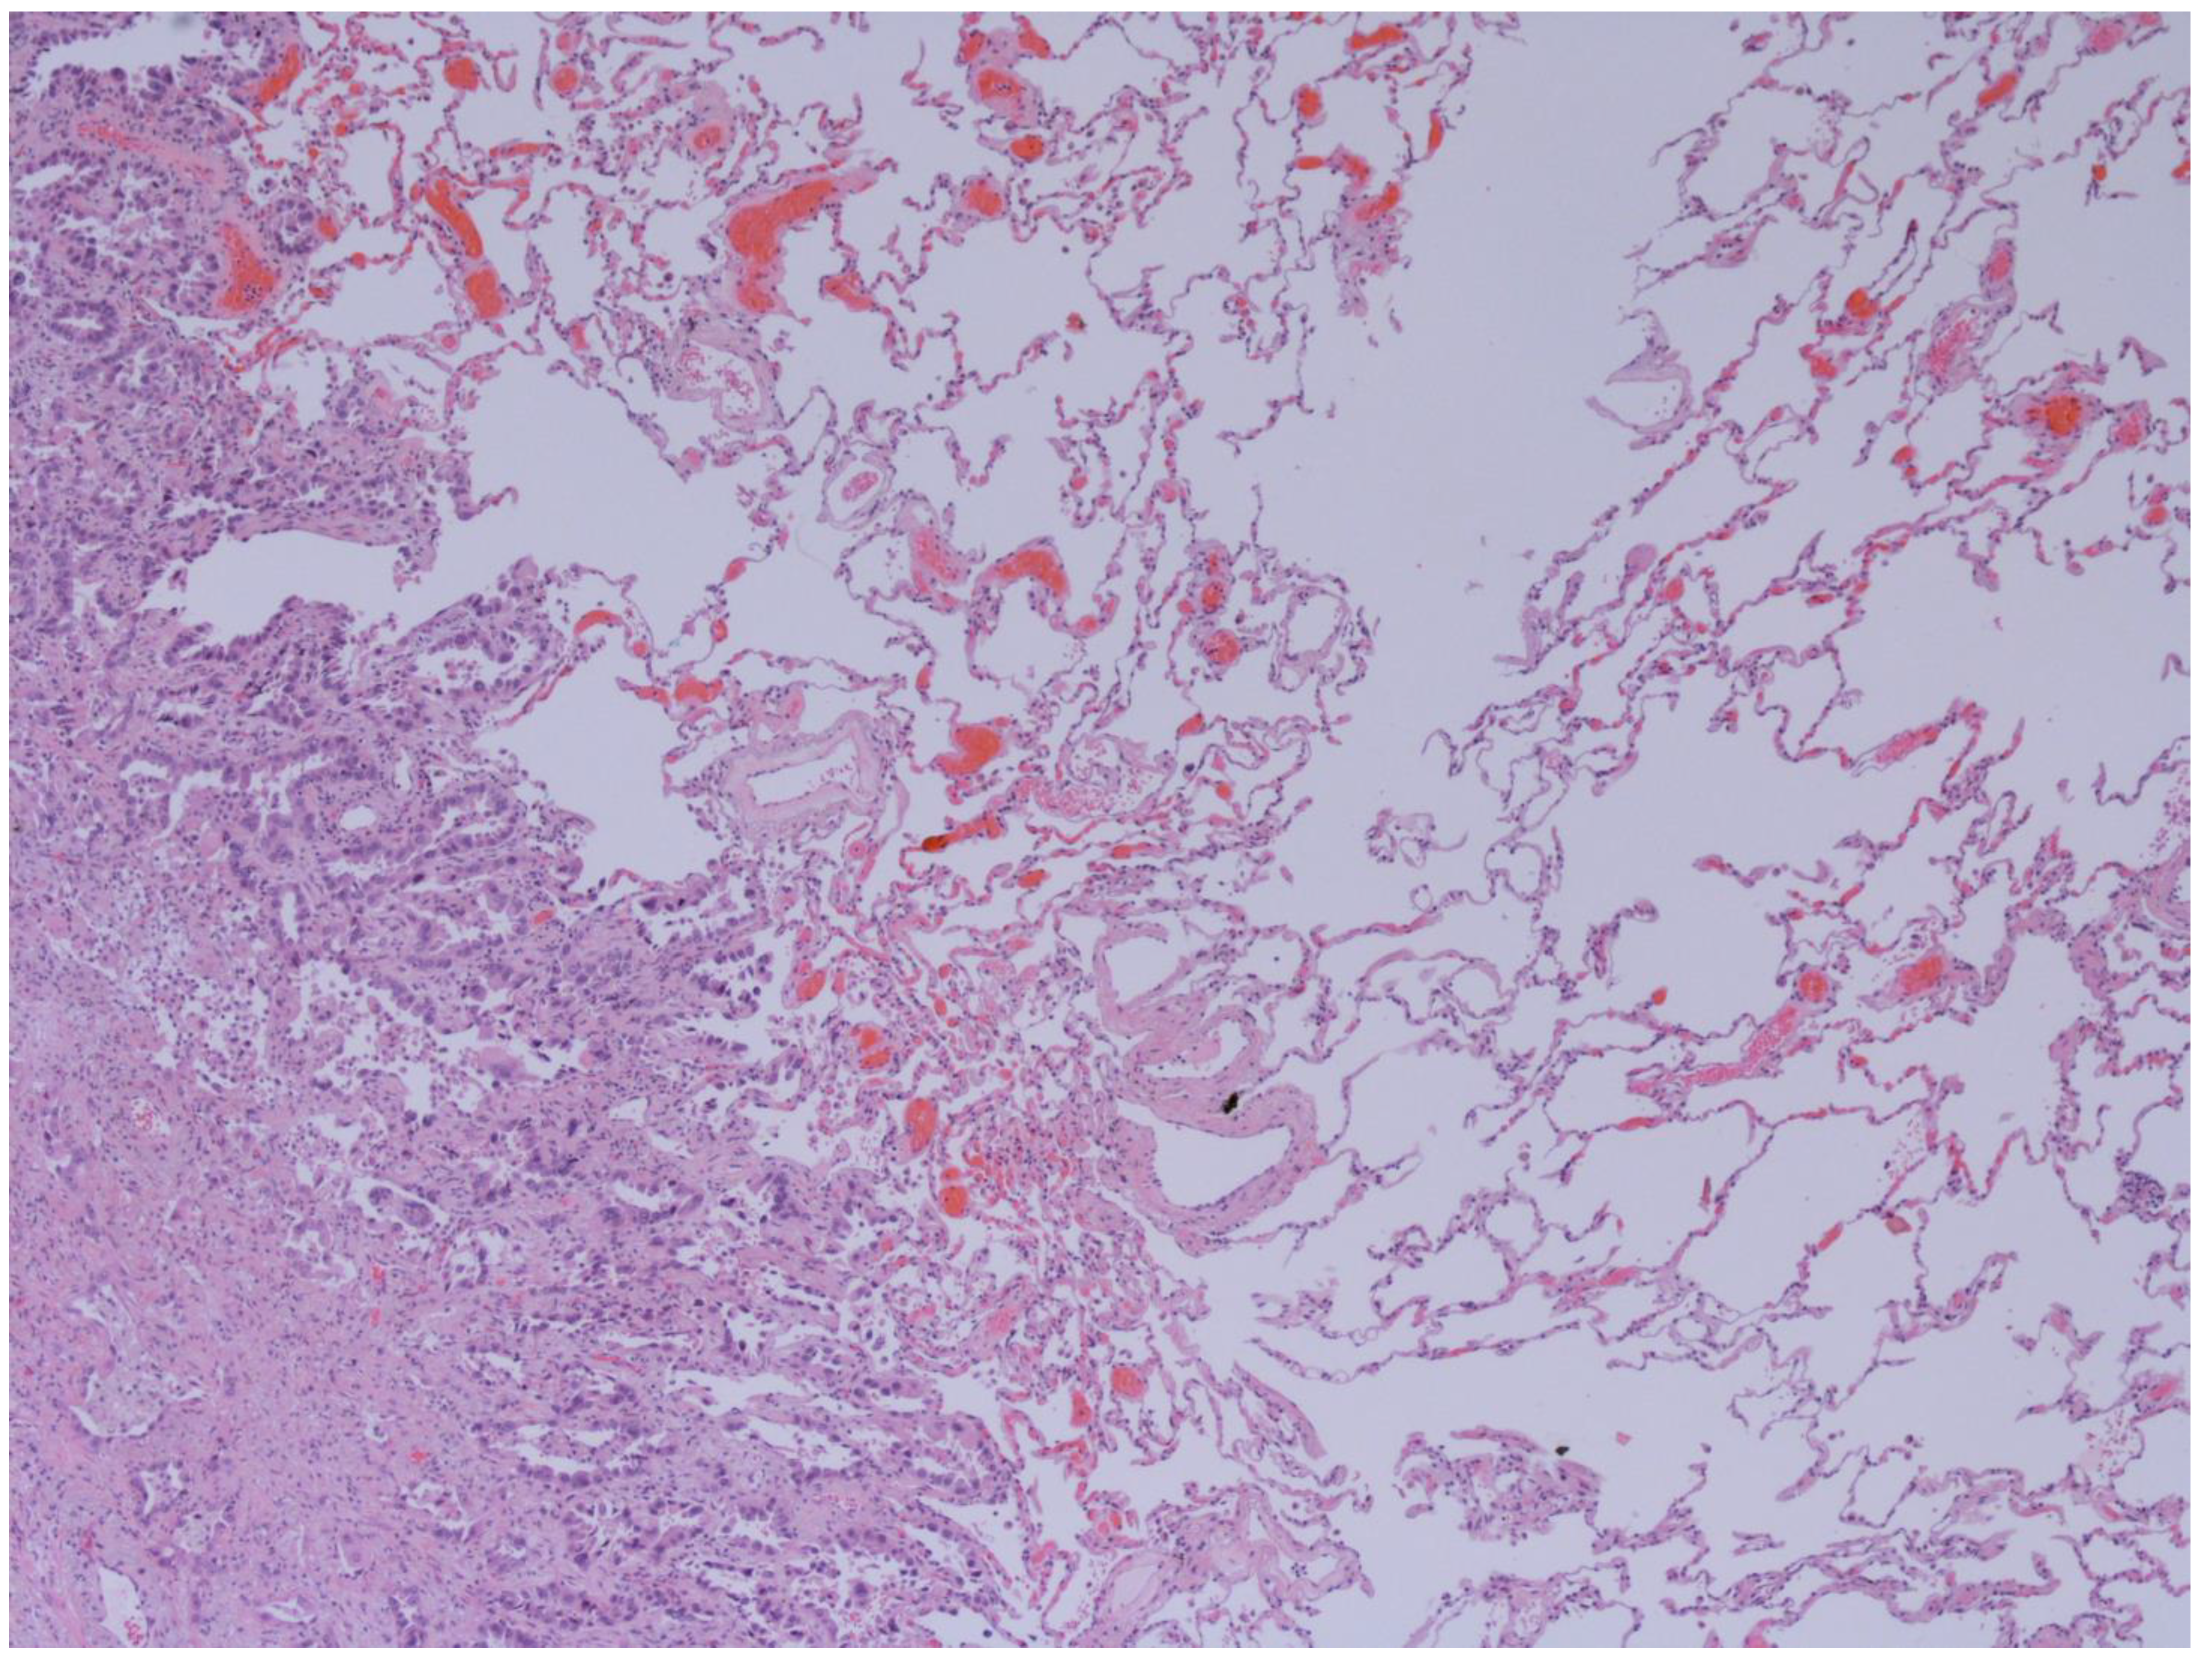

3.7. Histological Subtypes of Lung Cancer in NCFB